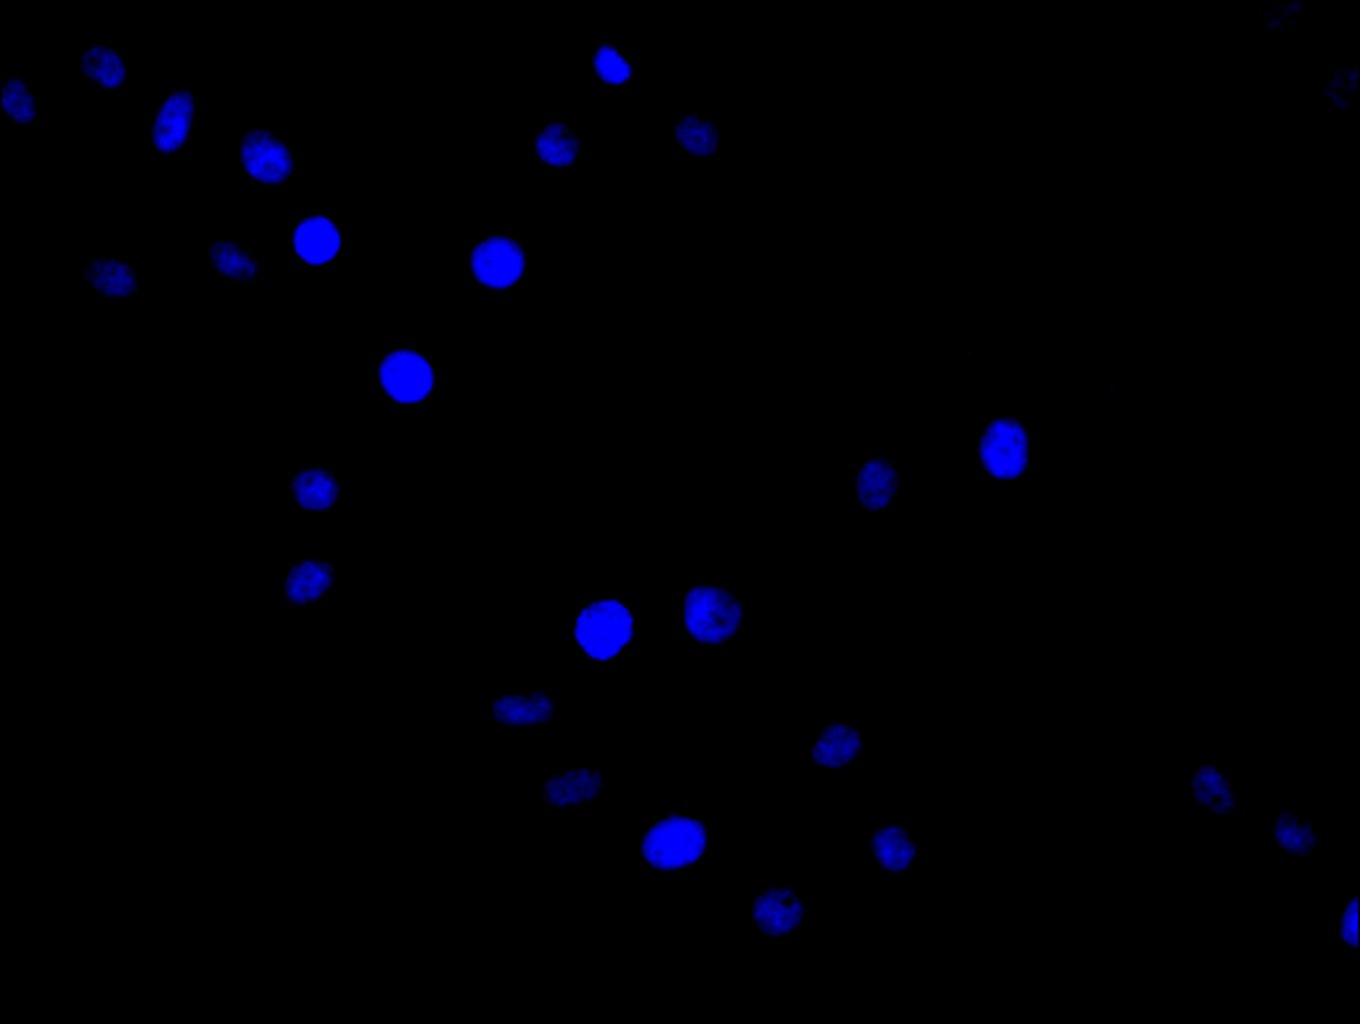

Immunofluorescence staining of Hela cell with CSB-PA015902ESR1HU at 1:30, counter-stained with DAPI. The cells were fixed in 4% formaldehyde and blocked in 10% normal Goat Serum. The cells were then incubated with the antibody overnight at 4C. The secondary antibody was Alexa Fluor 488-congugated AffiniPure Goat Anti-Rabbit IgG(H+L).

Immunofluorescence staining of Hela cell with 5% goat serum, counter-stained with DAPI. The cells were fixed in 4% formaldehyde and blocked in 10% normal Goat Serum. The cells were then incubated with the antibody overnight at 4C. The secondary antibody was Alexa Fluor 488-congugated AffiniPure Goat Anti-Rabbit IgG(H+L).